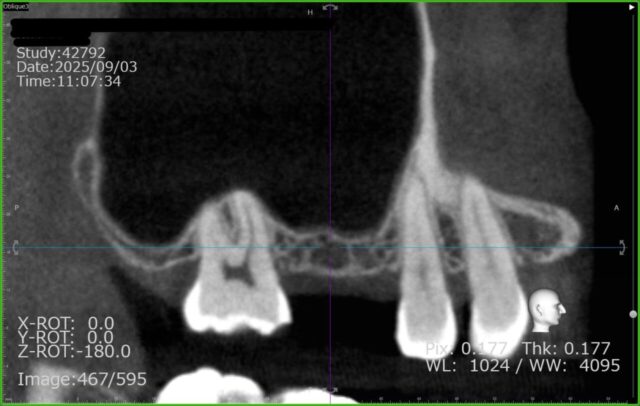

この患者さんの骨の高さは 3.8ミリ しかありませんでした。

しかし、今回予定している カムログ社のインプラント は、最短でも9ミリ の長さが必要です。(理想を言えば骨は11ミリ必要)

そのため、骨が約5ミリ分足りない状態でした。今回は CAS-KIT を使って、上顎洞の膜を破らずに約6ミリ分、空洞の底を持ち上げ、

そのスペースに人工骨(骨補填材)(バイオスL)を充填して骨を増やす処置を行いました。(通法では3ミリ程度の挙上が限界です)今回の施術時間は38分でした。

施術前のCT画像